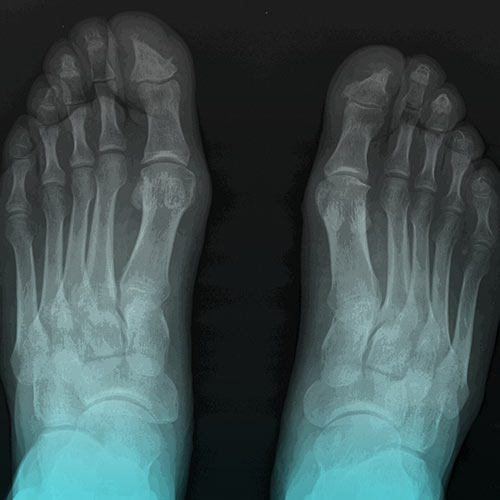

سپس پزشک از اشعه ایکس به منظور بررسی فرسایش در ستون فقرات و مفاصل دردناک شما استفاده میکند. اگر بیماری در مراحل اولیه باشد ممکن است فرسایش تشخیص داده نشود. این احتمال وجود دارد که بررسی توسط MRI نیز انجام شود. با این حال تفسیر نتایج MRI اغلب دشوار است.

یک آزمایش خون به نام بررسی میزان رسوب گلبولهای قرمز “erythrocyte sedimentation rate” ممکن است در جهت سنجش وجود هرگونه التهاب انجام گردد. این احتمال وجود دارد که آزمایش خون به منظور تشخیص و بررسی پروتئین HLA-B27 انجام شود. با این حال آزمایش مثبت HLA-B27 به این معنی نیست که شما به اسپوندیلیت آنکیلوزان مبتلا هستید. نتیجه مثبت این آزمایش نشان میدهد که شما ژن تولید کننده این پروتئین را دارید.

تشخیص این نوع آرتروز ممکن است مدتی طول بکشد. درباره آزمایشات و روشهایی که ممکن است استفاده شود بیشتر مطالعه نمایید و با پزشک خود مشورت کنید.